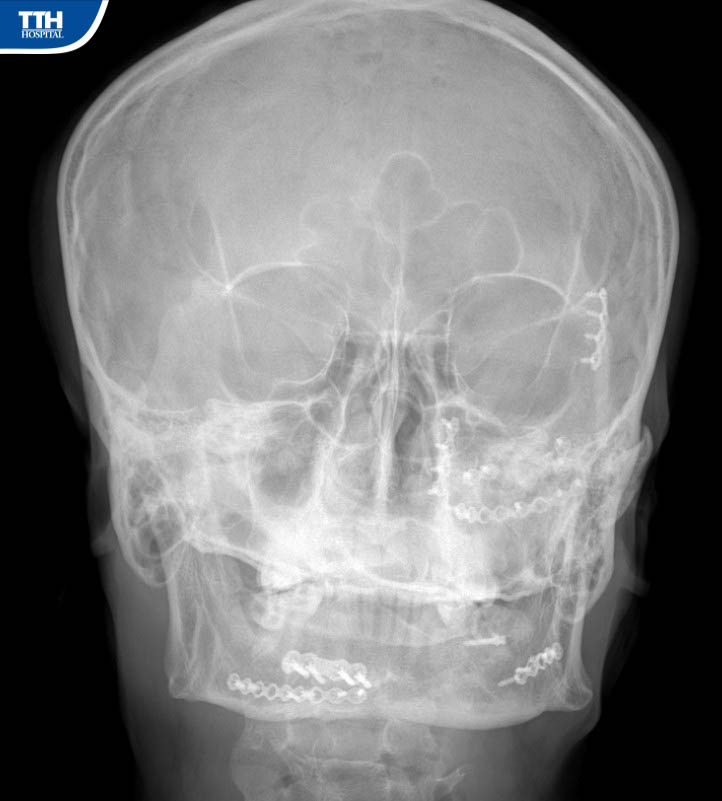

Vừa qua, Bệnh viện Đa khoa TTH Hà Tĩnh tiếp nhận bệnh nhân H.Đ.H (47 tuổi, Hương Khê, Hà Tĩnh), bệnh nhân cho biết lý do nhập viện khoa Răng Hàm Mặt là vì: ‘‘Cách đây 15 tháng đã đến Bệnh viện Hữu Nghị Việt Đức mổ kết hợp xương vùng hàm mặt, trước khi ra viện các Bác sĩ phẫu thuật nói: khi nào tháo nẹp vít thì ra Hà Nội tháo chứ tuyến dưới không tháo được". Đã đến kỳ hạn tháo nẹp vít kết hợp xương, qua tìm hiểu và được người nhà giới thiệu nên tôi quyết định đến Bệnh viện Đa khoa TTH Hà Tĩnh để tháo’’.

Theo BSCKI Trần Đức Hải – Khoa Răng Hàm Mặt Bệnh viện Đa khoa TTH Hà Tĩnh cho biết: ‘‘Ca phẫu thuật tháo phương tiện kết hợp xương phức tạp, gãy cả xương hàm trên trái và gãy xương hàm dưới 2 bên đòi hỏi kíp phẫu thuật có trình độ chuyên môn sâu về lĩnh vực hàm mặt, bởi gần như các đường rạch đều được dấu kín bằng đường trong miệng để tránh tạo sẹo ngoài da ’’.

‘‘Ca phẫu thuật diễn ra thuận lợi trong khoảng gần 90 phút. Sau phẫu thuật tháo phương tiện kết hợp xương hàm mặt, người bệnh hồi phục nhanh, từ ngày thứ 2 sau mổ. Sau 3 ngày, người bệnh có thể đi lại, sinh hoạt và xuất viện’’. Bs Hải cho biết thêm.